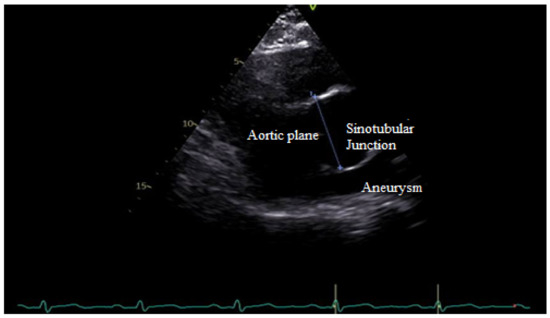

TTE determines the morphology of the valve, the connected hemorheology, the anatomical features of the root system, the diameter and the wall alteration of ascending aorta, and conditions like the aortic coarctation associated with BAV. In aortic root determination, TTE allows for measuring the sinotubular junction (STJ), especially in some aortopathy related to BAV (Figure 6).

Figure 6.

TTE shows enlargement of the sinotubular junction related to R-L cusp fusion.